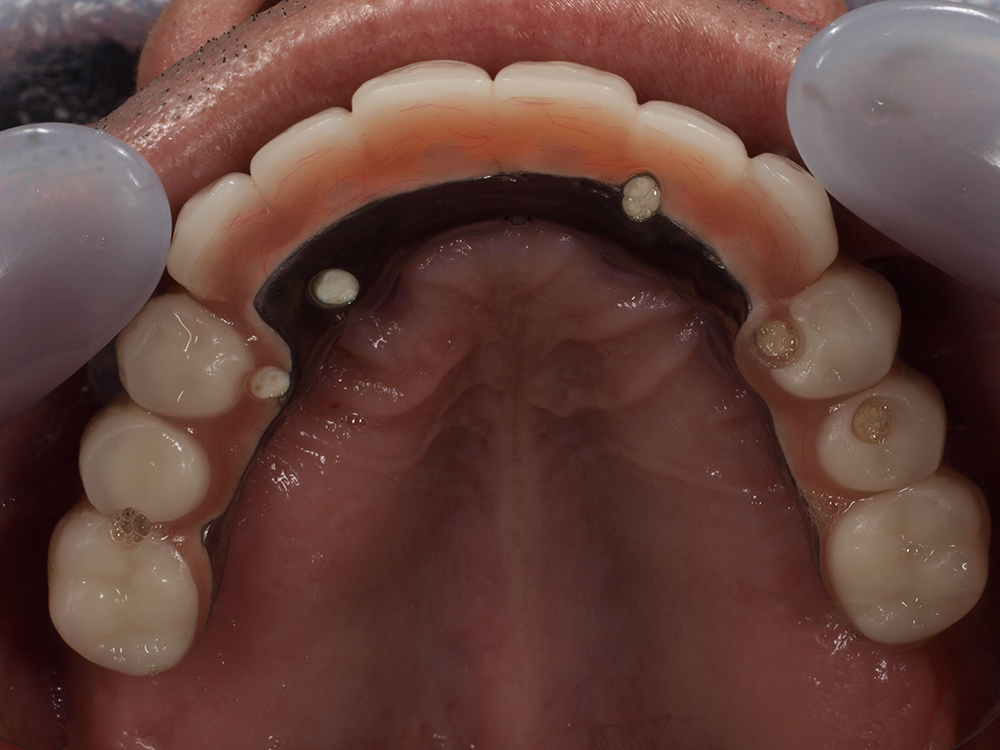

オールオン4は、片顎につき最少4本のインプラントで連結ブリッジを固定し、失われた歯列をまとめて再建する方法です。

骨がしっかり残っている部位を選び、奥歯には角度をつけて埋入することで安定性を確保します。手術当日に仮歯を装着できるため、歯のない期間を過ごす必要がありません。

1日で歯が稼働する

オールオン4は、インプラントを埋め込んだその日に人工歯を入れられる可能性がある処置です。そのため、歯のない期間を過ごす必要がありません。インプラントの配置設計、硬い骨の選択、強固な上部構造(人工歯)での固定によって可能になります。

お手入れのしやすさと清潔感

オールオン4は、お口の手入れを簡素化できるので、清潔さを維持しやすくなります。インプラントの埋入本数が片顎最少4本と少ないため、清掃する本数が少なく、管理が楽になります。その結果、清潔を保ちやすい状態となり、インプラントが長持ちしやすくなります。